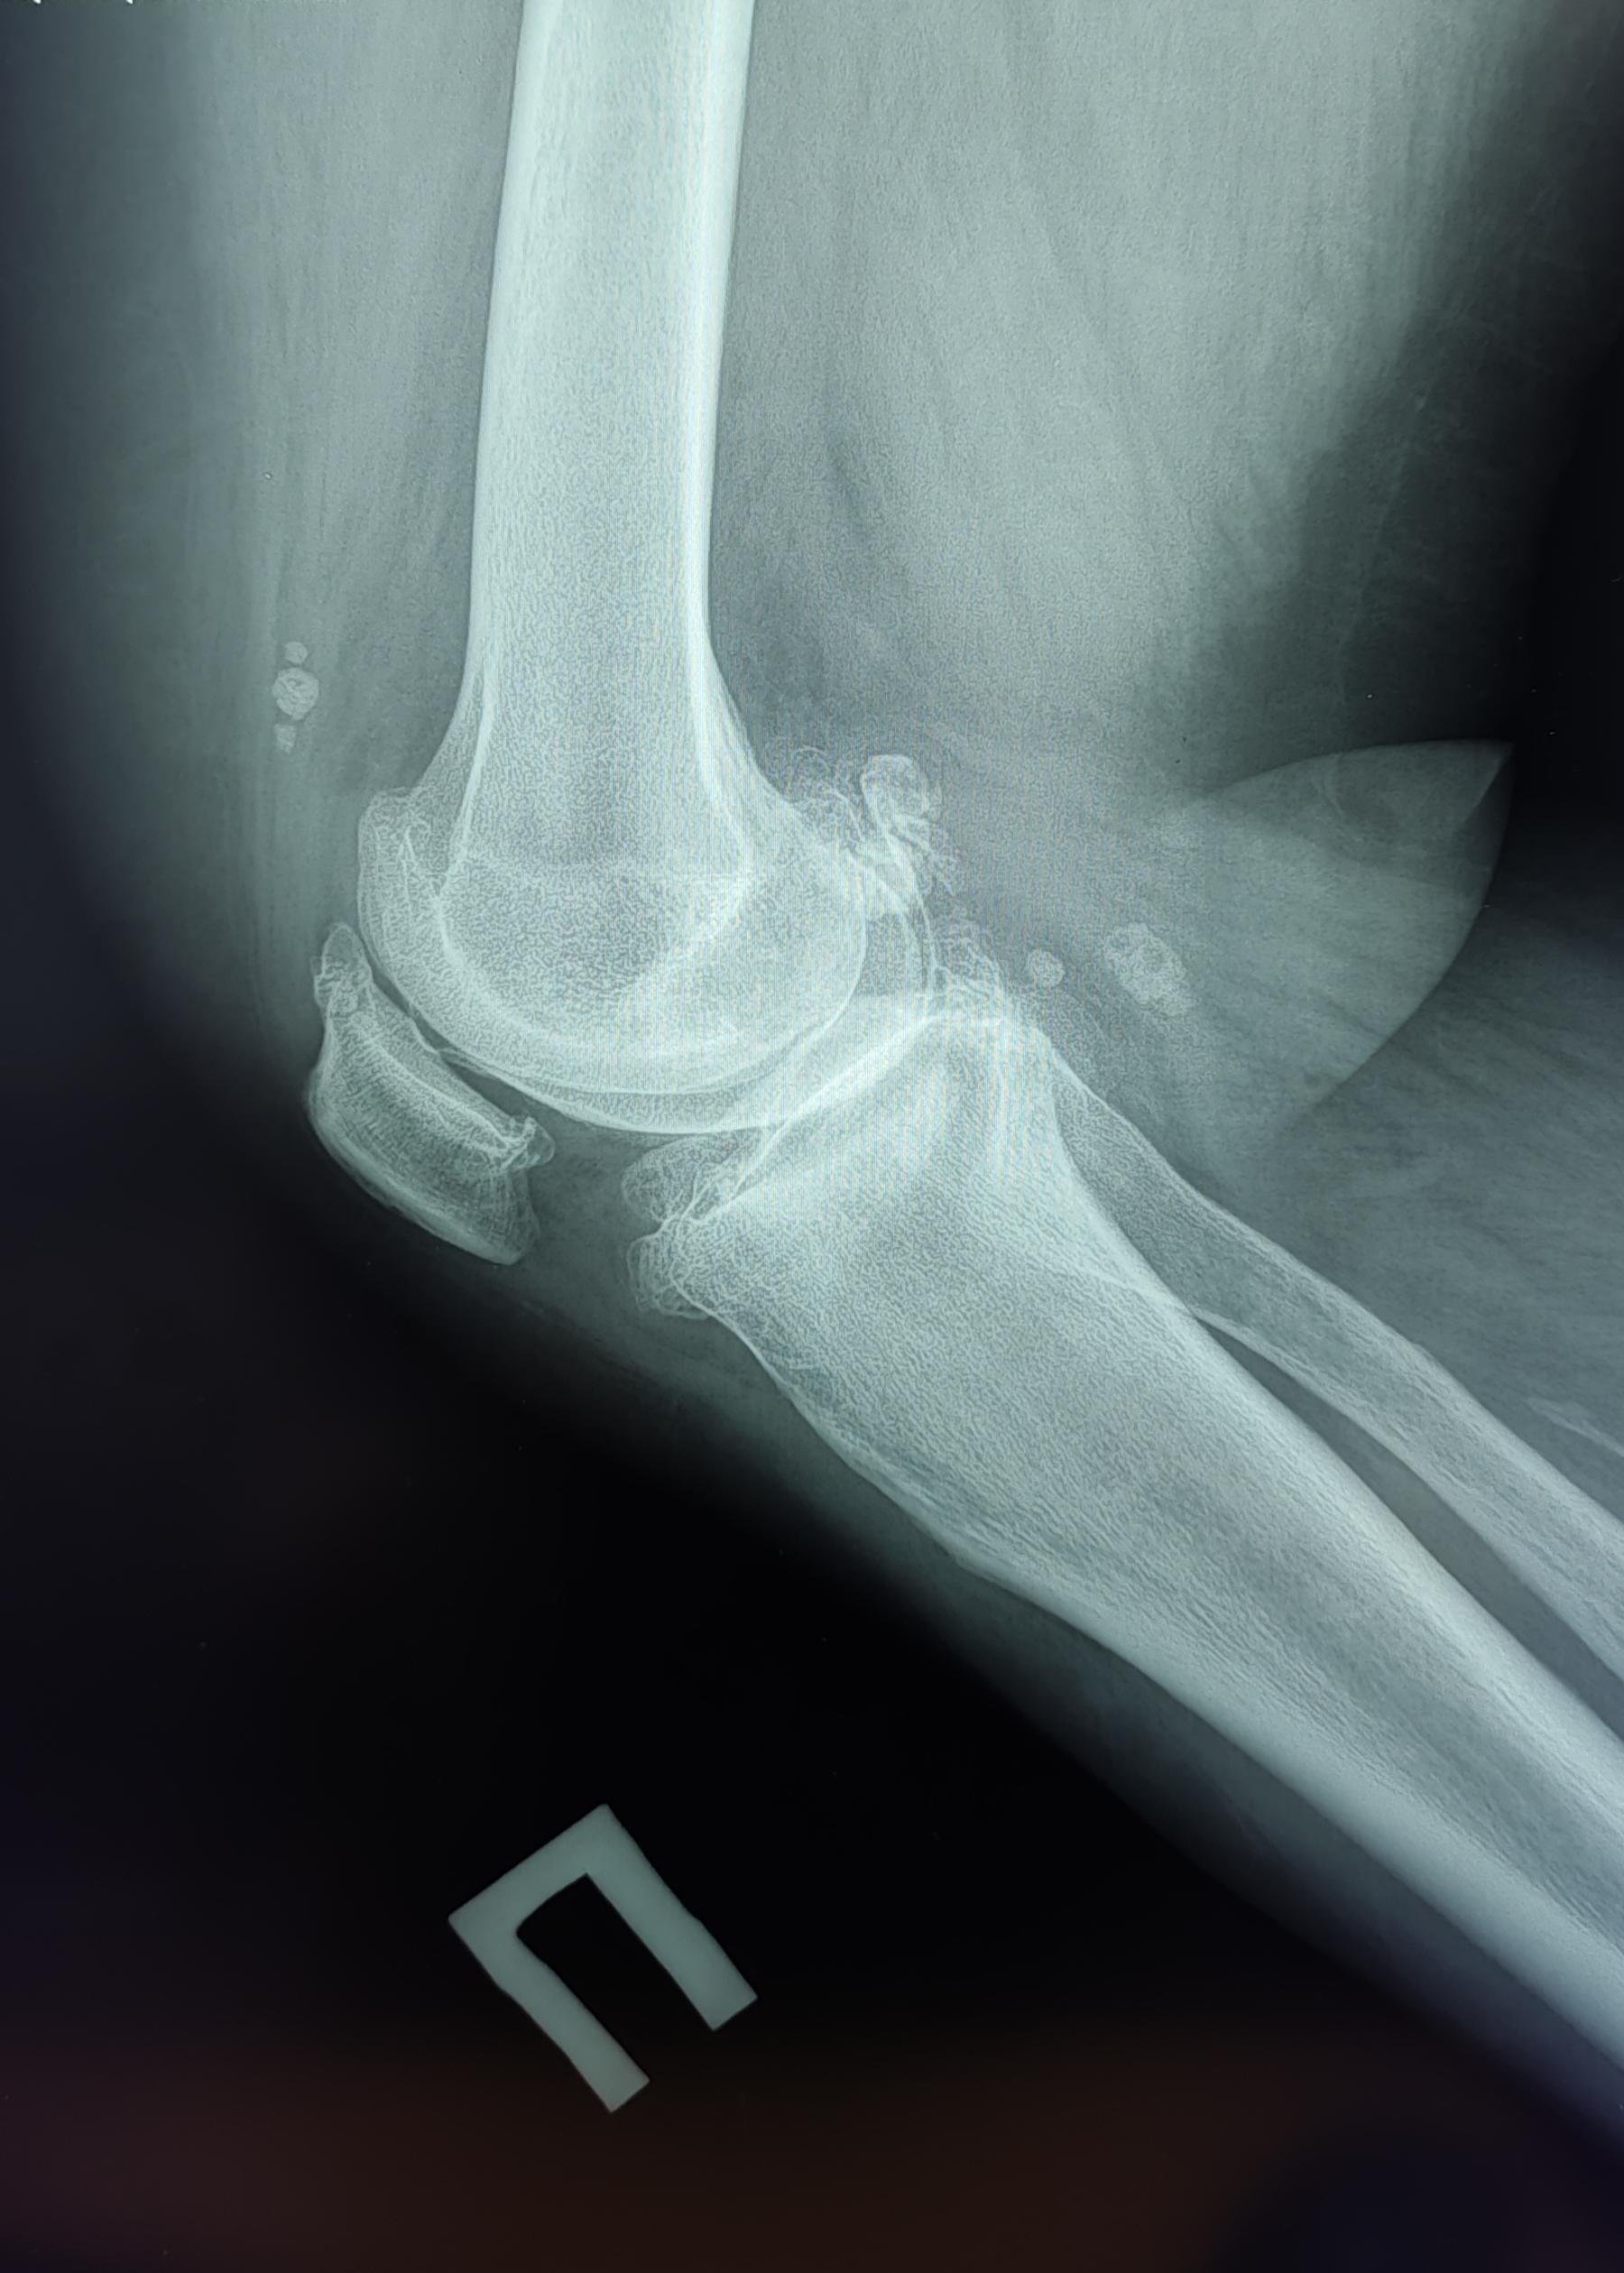

Описание: На Р-граммах правого к/с в 2х проекциях: Значительное сужение суставной щели в медиальных отделах до 1.6 мм, субхондральный склероз, краевые костные разрастания, заострение полюсов надколенника, уплотнение его внутренней поверхности ,по ходу внутренней поверхности синовиальной оболочки визуализируются единичные округлые хондроматозные тела №~7,размером от 5 мм до 25 мм в диаметре. Заключение: Хондроматоз правого коленного сустава. Гонартроз справа 3 ст. по Kellgren.Пателло-феморальный артроз.